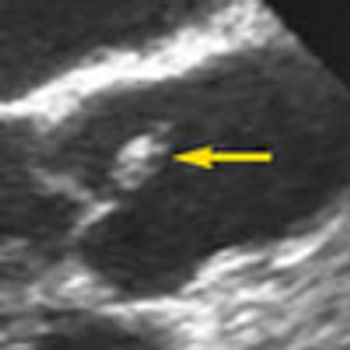

An 18-year-old woman from Mexico was hospitalized because of severe headache with nausea and vomiting. Her headaches had started 4 years earlier and had progressively worsened. They occurred mainly in the occipital region and were pulsating, worse on bending down, and unrelieved by any medication. They were often accompanied by dizziness and presyncope.